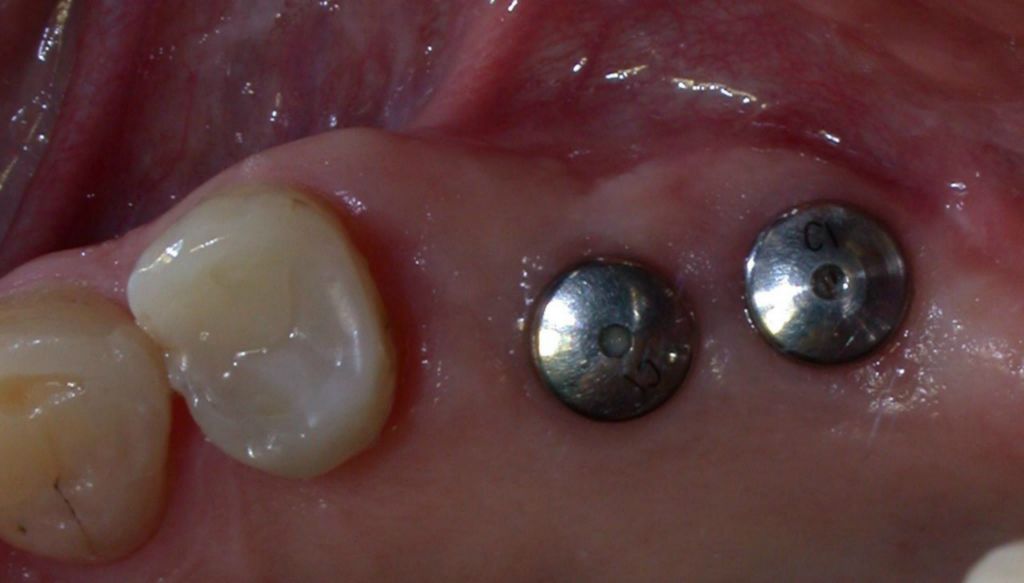

Zirconia Implants